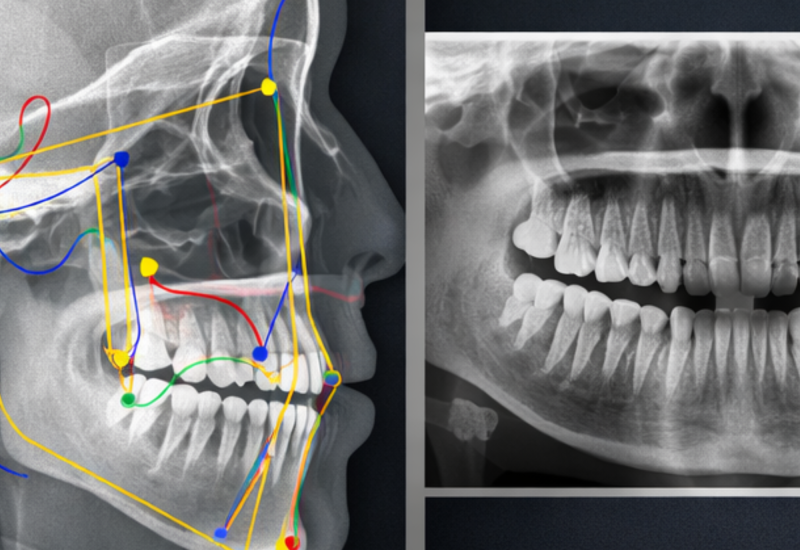

O grande diferencial está na integração entre e Medicina do Sono com diagnósticos mais precisos e tratamentos mais eficazes.

Mestre e Doutora pela USP, Ortodontista em DTM e Odontologia do Sono aqui em Araçatuba. A Dra. Bruna atua de forma integrada, acolhedora e personalizada, buscando sempre tratar o paciente de forma completa: estética, funcional e respiratória.